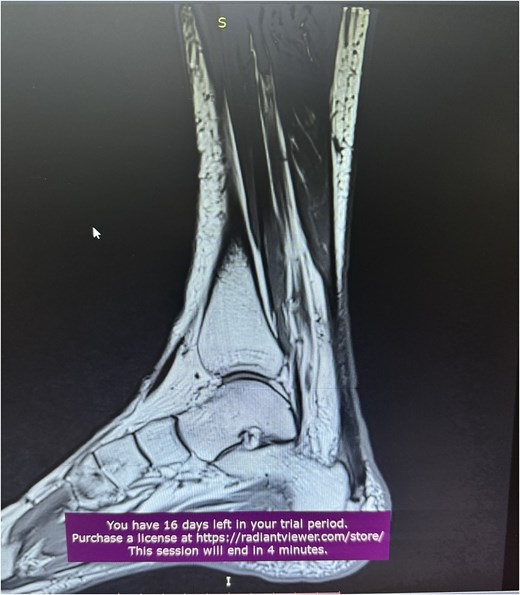

A 68-year-old female presented to the emergency department with significant discomfort localized to the Achilles tendon region. Her medical history was relatively uneventful, except for hypothyroidism and a previous diagnosis of Achilles tendinopathy (Fig. 1), that was treated conservatively with ten daily sessions of percussive ultrasound therapy. More specifically radial extracorporeal shockwave therapy (ESWT) was used, with 2.000 shockwaves at 12 Hz, which was followed by physical therapy exercises and ice therapy. Following the therapeutic sessions, the patient experienced acute symptoms, including a pronounced popping sensation and significant functional impairments.

A comprehensive physical examination provided significant insights into the patient’s condition following the Achilles tendon rupture. The Thompson test was particularly noteworthy, showing an absence of plantar flexion upon calf compression, strongly indicating a complete tendon rupture. The examination further revealed a palpable gap in the Achilles tendon and increased passive dorsiflexion. Symptoms included significant weakness, difficulty walking and heel pain. Imaging studies, including X-rays (Fig. 2) and magnetic resonance imaging (MRI) (Fig. 3), confirmed these findings, showing an acute rupture with retracted tendon edges, distinguishing it from chronic condition and suggesting a possible link to the vigorous ultrasound therapy [3].